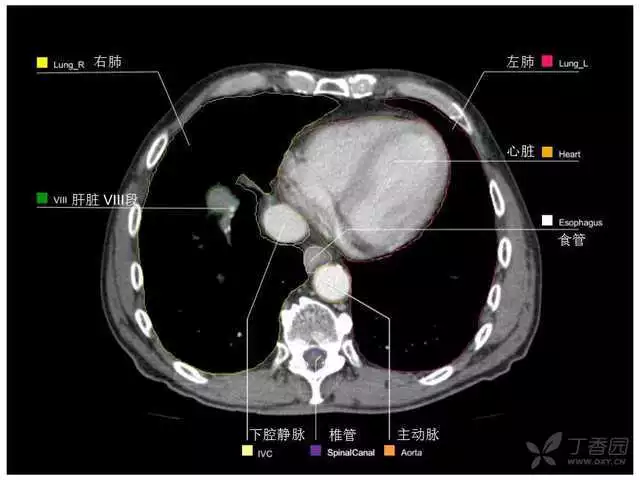

其实你离掌握上腹部 CT 影像只有一套高清实用图谱的距离,下面把我最喜欢的这本图谱分享给大家,为了方便阅读,我加了中文标识。后面附赠几张血管相对位置解剖关系图片,帮助大家理解(文中多图,建议在 wifi 环境下查看)。